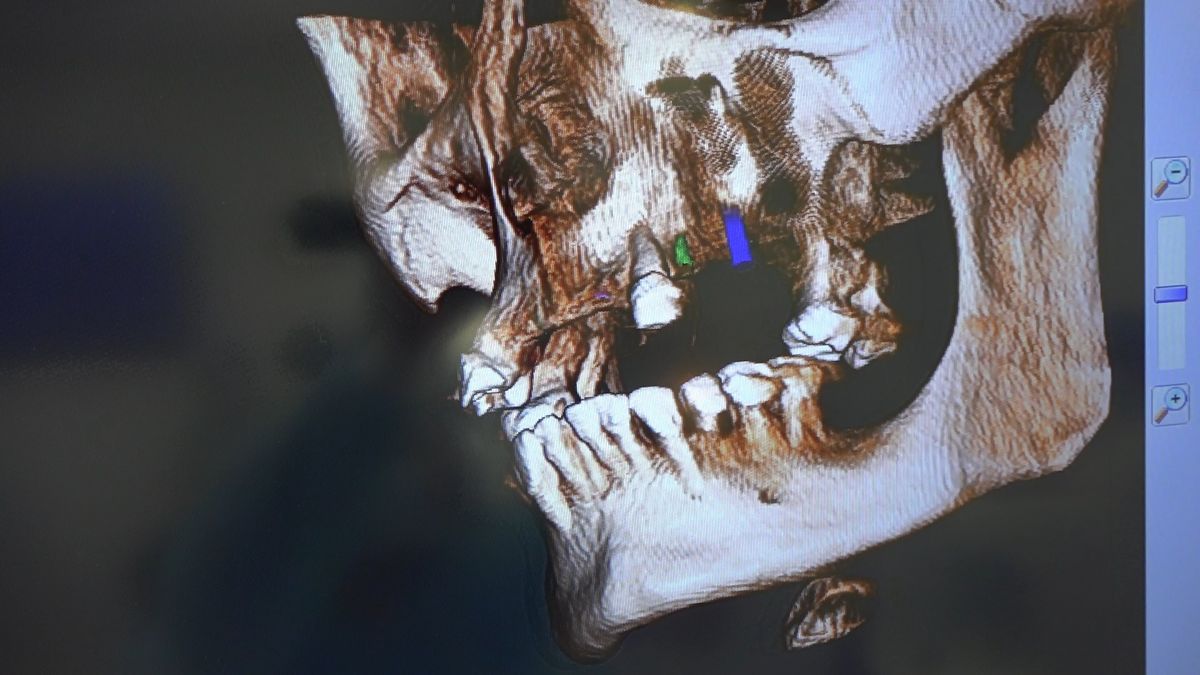

Pierwszy weekend 2019 roku w Instytucie Vivadental, to doskonałe otwarcie kolejnego roku edukacyjnego i szkolenia naszych Kursantów. W drodze do sukcesu w implantologii zdobywają wiedzę i umiejętności, a każdy kolejny zabieg to impuls i inspiracja do twórczego rozwoju w leczeniu własnych Pacjentów. Rozpoczęliśmy od sesji praktycznej implantologicznej właśnie z udziałem Pacjentów, na której dominowały samodzielne zabiegi wykonywane pod kierunkiem Mentorów – dr n.med. Violetty Szycik i dr n.med. Magdaleny Kisłowskiej – Syryczyńskiej. W ciągu dwóch dni zabiegowych przyjęliśmy 14 Pacjentów, przeprowadziliśmy zabiegi chirurgiczne, zabiegi regeneracyjne tkanki kostnej i augmentacji oraz wszczepiliśmy 20 implantów systemu Axiom. W ramach panelu edukacyjnego Sukces Twojego Biznesu odbyły się kolejne zajęcia z NLP, na których nasz Mentor Mariusz Wójcik z Gdańskiej Akademii Umiejętności Menedżerskich, kontynuował wprowadzenie do psychologii i podstaw kierujących decyzjami Pacjentów. Ćwiczenia w wesołej i koleżeńskiej atmosferze były niezwykle pouczające, a jednocześnie stanowiły idealną odskocznię po wyczerpujących zabiegach.